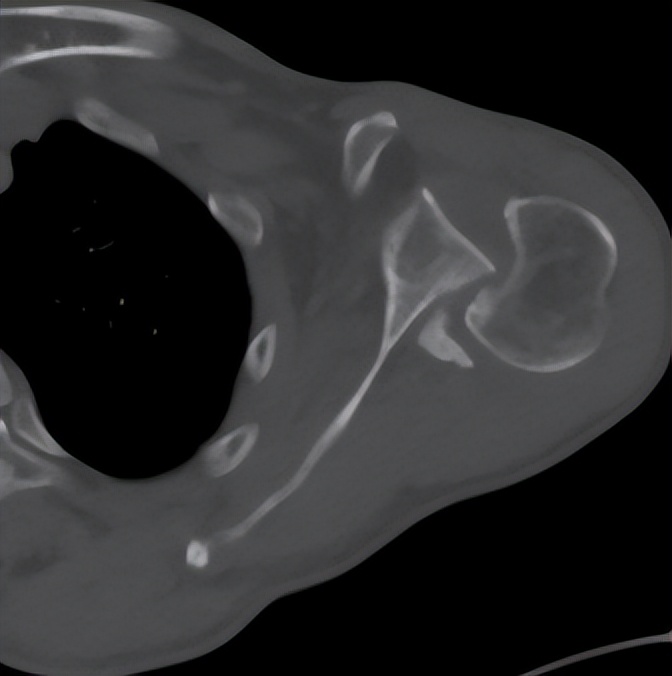

面对这例受伤时间长、脱位类型少见、骨折情况复杂的患者,创伤中心常务副主任李连欣组织全科病例讨论,通过分析认为该患者为“陈旧性绞锁性肩关节后脱位合并肱骨头骨折(反Hill-Sachs损伤)”,患者疼痛活动障碍,不能继续保守治疗,需要进行手术。患者的手术难点在于:患者为陈旧性后脱位,周围组织已经严重粘连、僵硬;脱位的肱骨头卡于关节盂造成关节面缺损,很难恢复肱骨头原本的解剖结构;合并肩袖巨大陈旧性撕裂,难以修复;患者为老年,骨质疏松明显;病程长达10年,即使手术勉强恢复其解剖关系,未来发生肱骨头缺血坏死、创伤性关节炎等并发症的几率极高。经过科室充分讨论分析,最终确定反式肩关节置换的手术方案。

肩关节脱位俗称脱臼,是临床常见损伤,后脱位少见,仅占肩关节脱位的2%, 合并肱骨近端骨折的罕见,其发病因素主要是外伤*力暴**及骨质疏松。一般临床上把骨折脱位时间在三周以上的称为陈旧性骨折或脱位。对于肩部脱位多数可以手法复位获得较好效果,新鲜骨折通过手术复位固定一般也可获得满意的效果,但对于陈旧性脱位或骨折,由于关节的挛缩、粘连等,骨折断端和周围存在大量瘢痕组织和骨痂,时间再长即导致畸形愈合,复位十分困难,也难以实施内固定。实施关节置换也存在软组织不平衡,脱位,神经损伤等风险,手术很有挑战性。